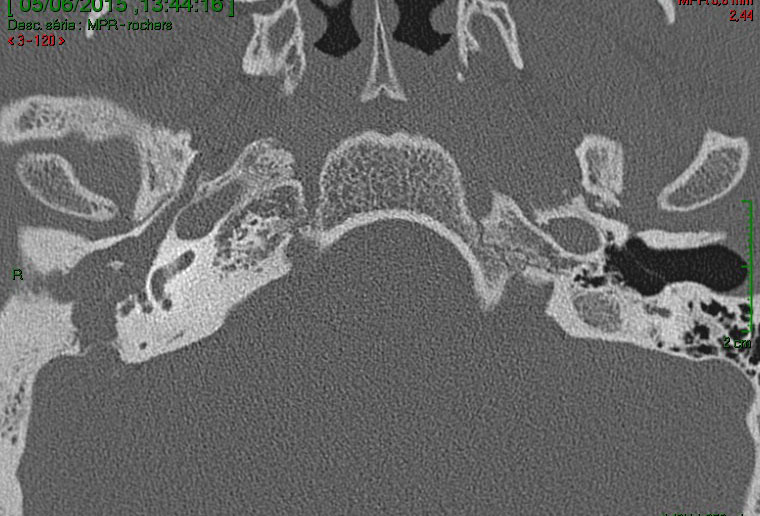

Devant ces atteintes multiples, vous demandez un scanner et une imagerie par résonance magnétique (IRM) en urgence qui sont représentés ci-dessous.

Question 11 : Qu’en pensez-vous ?

Question difficile, à laquelle on peut (et doit) répondre avec la clinique. En effet, le canal est ouvert sur le scanner (en coupe coronale sur la figure 4), mais surtout on peut le déduire devant le fait que le patient a un nystagmus avec un cholestéatome

La cavité de l’oreille est noire : donc il y a de l’air. Elle n’est pas comblée par du tissu

Faux, le scanner montre un comblement aspécifique, sans différencier tissu, liquide ou fibrose

Avec la séquence de diffusion à droite, qui est pathognomonique du cholestéatome

C’est une séquence de diffusion

L’IRM est le seul examen pathognomonique du cholestéatome. Le scanner montre la lyse osseuse mais n’est pas du tout spécifique de l’atteinte. Il n’est pas nécessaire de connaître les structures de l’oreille interne sur le scanner (qui sont très compliquées), mais il faut au moins reconnaître une oreille moyenne pleine (contenu gris) d’une oreille saine aérée (contenu en noir). On peut ensuite déduire de l’énoncé les destructions correspondantes. On aurait pu aussi dire dans cette question que le canal du nerf facial était détruit : c’est forcément le cas puisqu’il y a une atteinte du facial.